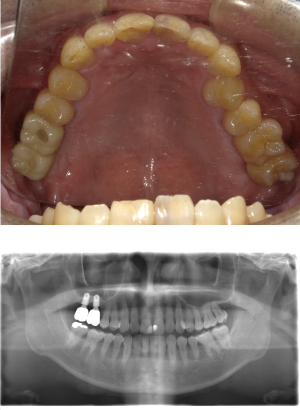

40代 女性 インプラント治療(右上64サイナス・GBR)

| 年代・性別 | 40代・女性 |

|---|---|

| 主訴 | 歯周病が進行し、抜歯適応となってしまったところにインプラント治療希望。 |

| 部位 | 右上⑥5④3② |

| 治療期間 | 約1年4ヶ月 |

| 費用 | ¥1,121,000(税込) |

| 副作用・リスク |

|